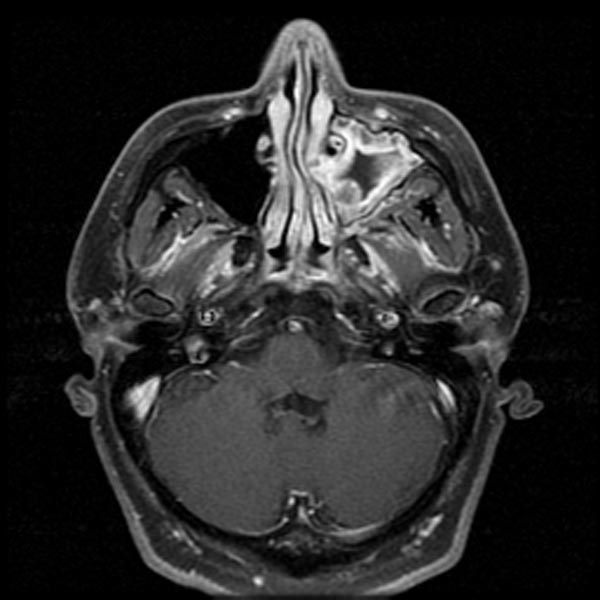

Компьютерная томография носоглотки: Что нужно знать